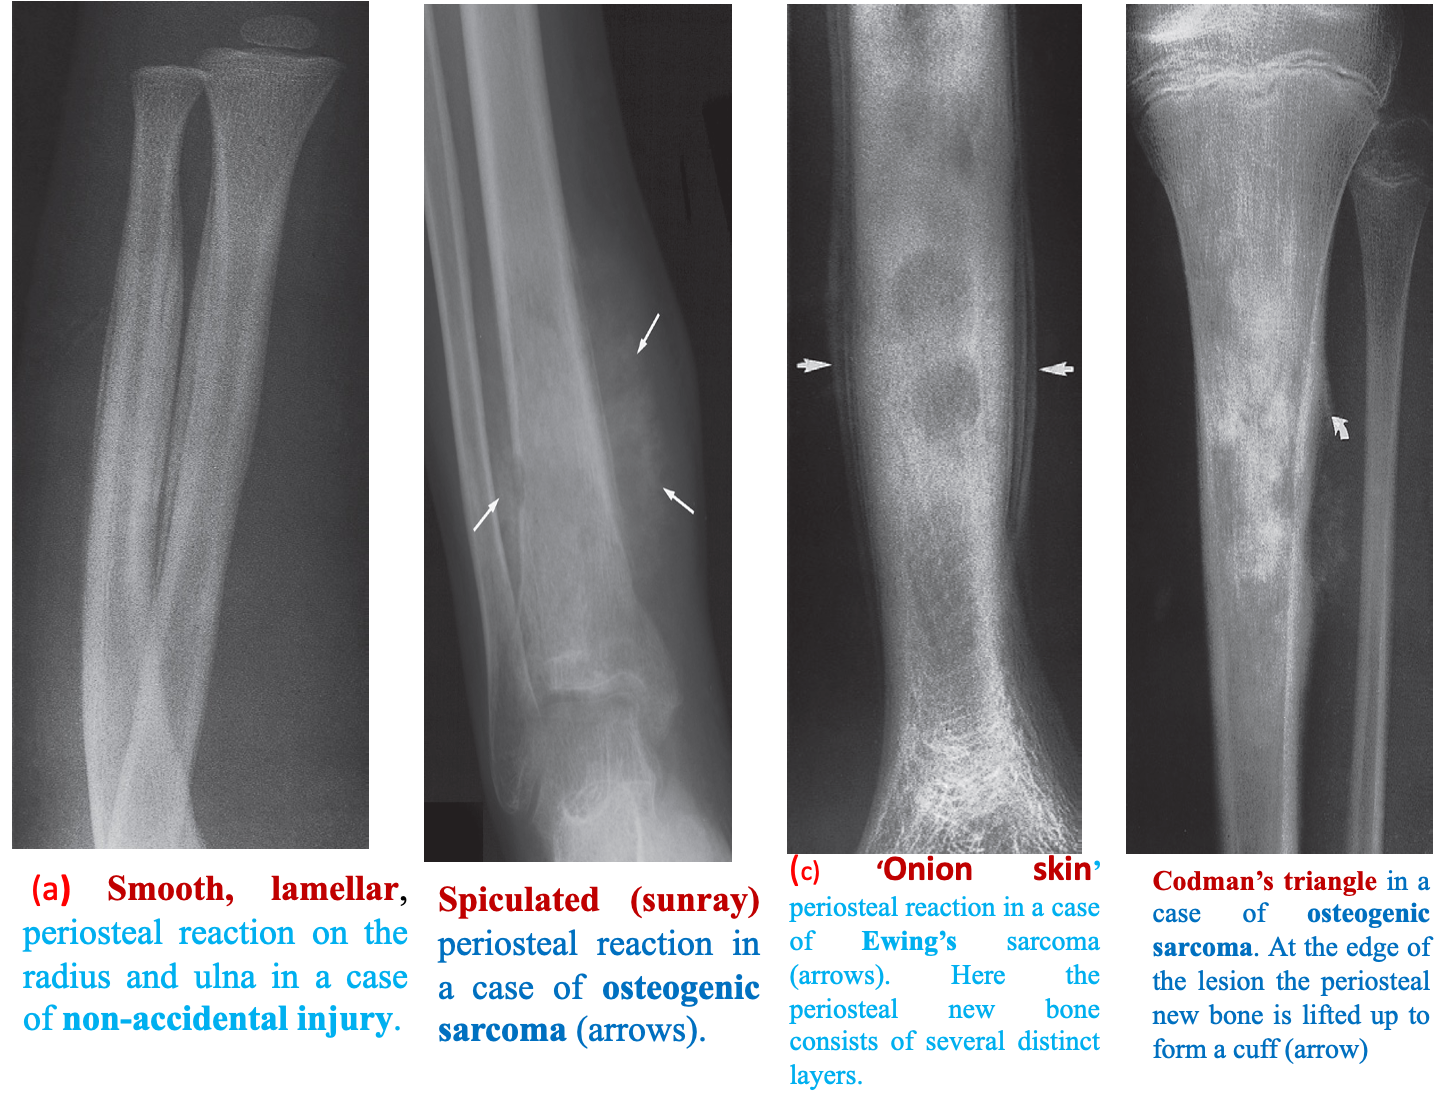

Refers to excess bone produced by the periosteum, which occurs in response to such conditions as neoplasm, inflammation or trauma.

- At the edge of a very active periosteal reaction there may be a cuff of new bone known as a Codman’s triangle.

- Often seen in highly malignant primary bone tumours, e.g. osteosarcoma

Smooth lamellar, Spiculated (Sunray) Onion skin, Codman’s Triangle Z

The presence of an active periosteal reaction in the absence of trauma usually indicates an aggressive lesion .